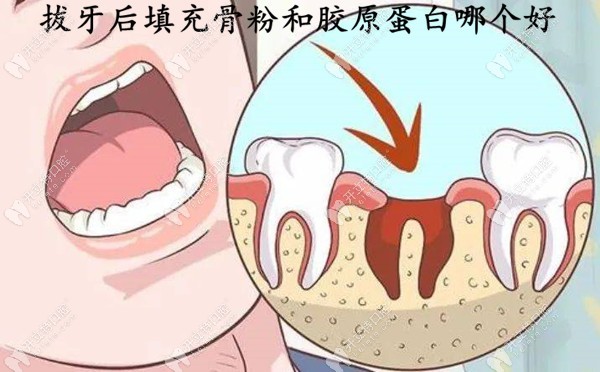

拔牙后填充骨粉和胶原蛋白哪个好?细说骨粉/胶原蛋白优缺点

拔牙后填充骨粉和胶原蛋白是目前比较常见的治疗方式,也有人比较想知道拔牙后填充骨粉和胶原蛋白哪个好。那本期内容就从骨粉和胶原蛋白的优缺点来分析吧。